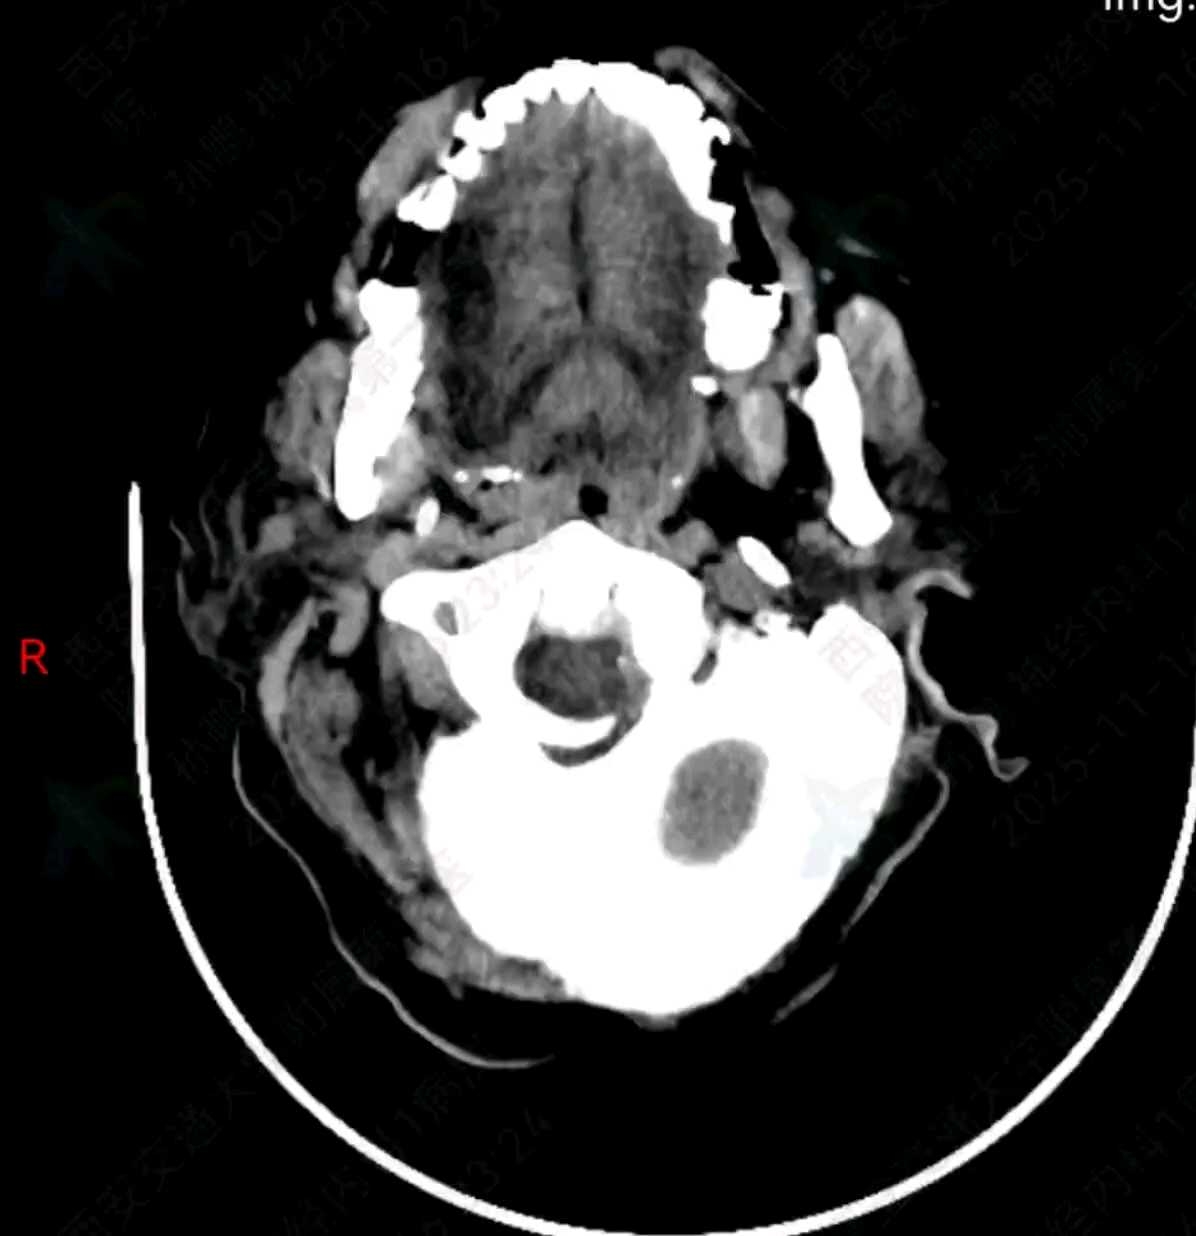

当日晚11:50上完卫生间后回到床上患者出现嗜睡,构音障碍明显加重,双眼向右凝视,左侧中枢性面瘫,左侧肢体不能活动,左侧病理征阳性。生命体征:血压:165/74mmHg,脉搏69次/分,呼吸19次/分。

急查CT

立即联系神经外科急会诊,暂予以脱水降颅压,乌拉地尔降压处理。

经过沟通后同意立即行颅内血肿清除术,术后转ICU加强治疗。术后查体:镇静镇痛状态,双侧针尖样瞳孔,直径约2mm,向右凝视回来了,左侧疼痛刺激无反应,右侧疼痛刺激有收缩。当日家属自动出院。